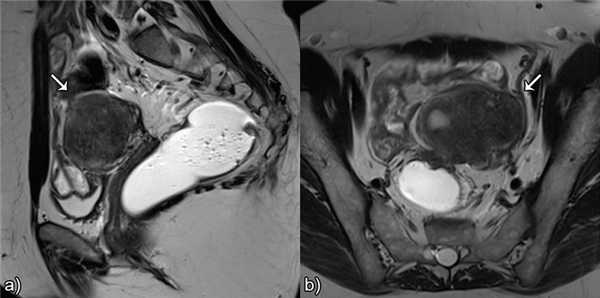

![]()

Рис.7 Сокращения матки, имитирующие аденомиоз: а) и b) сагиттальные T2 взвешенные изображения, гитпоинтенсивные полосы, перпендикулярные к переходной зоне, исчезающие/изменяющиеся через несколько минут, представляют собой физиологические сокращения матки.

Рис.8 Псевдо-расширение эндометрия: сагиттальные T2 взвешенные изображения, утолщение переходной зоны с полосатыми участками высокой интенсивности сигнала, расходящимися от эндометрия по направлению к миометрию, имитирующими инвазию рака эндометрия.